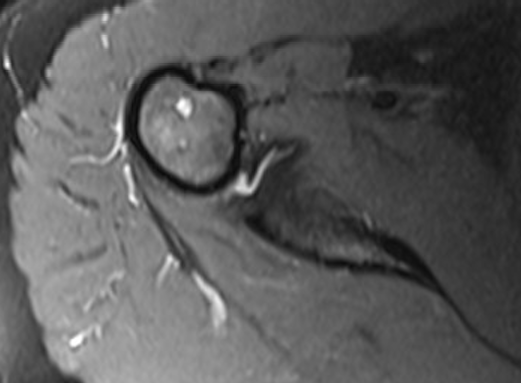

Analyse eines Therapievergleichs in der nichtlinearen Systemdiagnostik und -therapie

Einsatz verschiedener NLS-Systeme zur Fehlerminimierung und Vergleich mit herkömmlichen diagnostischen Verfahren wie der Magnetresonanz-tomografie (MRT) und Röntgen